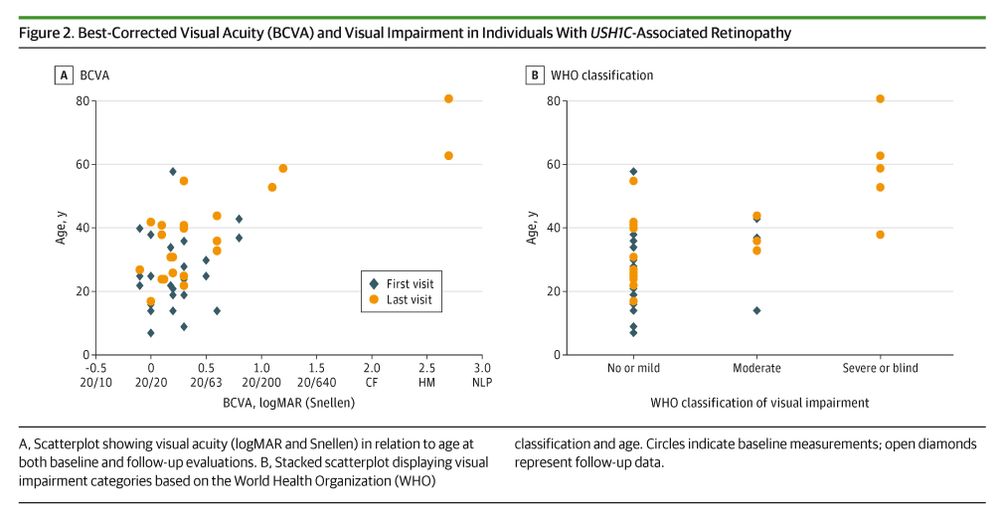

ja.ma/3Mn83Ys

ja.ma/3Mn83Ys

ja.ma/43V9hQS

ja.ma/43V9hQS